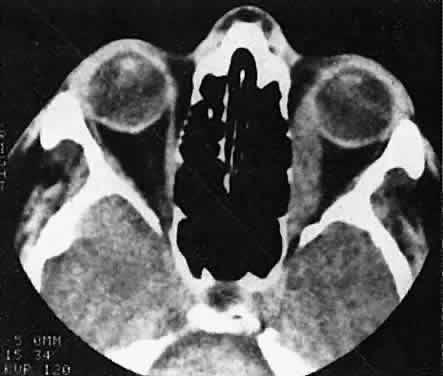

Acute blood cyst formation in this age group makes the distinction between a pre-existent but clinically silent lymphangioma and a rapidly emerging rhabdomyosarcoma a common orbital diagnostic problem. Evidence suggesting an orbitallymphangioma includes the variable finding of conjunctival or eyelid components of the malformation.86 Conjunctival lesions appear as ectatic channels filled with clear or hemorrhagic fluid. Eyelid ecchymosis may result from the seepage of blood out of the thin-walled orbital cysts. Additional developmental anomalies of the eye and adnexa may be present. Other head and neck involvement may be manifest as local hypertrophy (e.g., of the cheek or lips), and cystic palatal lesions may be seen. CT discloses a single or multilobulated mass, which represents only the blood cyst portion of the tumor (Fig. 14). Individual lobules may have different radiodensities depending on the presence of clots or liquefied blood within each cyst (Fig. 15). A generalized increase in orbital dimensions suggests a long-standing, probably congenital process. Echography may help differentiate the cystic components of lymphangioma from cellular rhabdomyosarcoma. Echography shows the blood cysts to be acoustically inactive spaces, with extremely low internal reflectivity (Fig. 16). Clots within the cysts can increase internal heterogeneity, however. MRI has virtually eliminated the need for diagnostic biopsy in this condition, because of its ability to show differing magnetic properties of suspended, degrading blood products (Fig. 17).